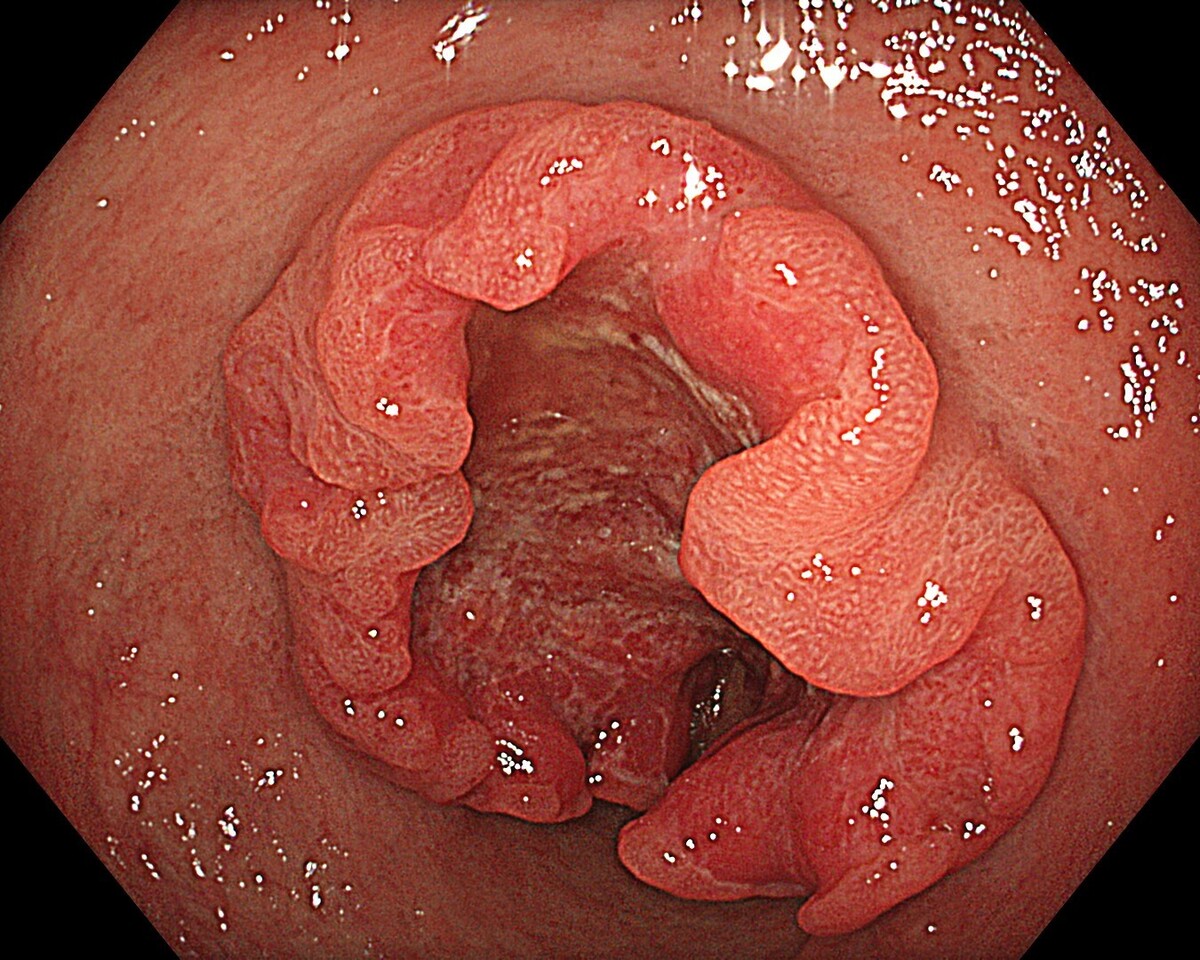

健診:PET-CT、MRI/MRA、胃内視鏡、大腸内視鏡

午前中に胃・大腸内視鏡を行い、午後にFDG-PET/CTを受ける1日完結プランです。PETを含むため、前日または当日の朝にホテルで下剤を服用します。内視鏡で消化管を精査しつつ、PETで全身のがんリスクを可視化できます。特に早期がん、転移、隠れた腫瘍の発見に有効で、全身を網羅的に評価したい方に適しています。

NEO HEALTHCAREは、大阪本町に位置する内視鏡専門クリニックです。 世界トップレベルの内視鏡技術とオリンパス社製の最新内視鏡機器により、最高水準の医療と快適な環境を提供します。

胃または大腸の内視鏡を鎮静下で行い、がん・ポリープ・炎症を精密評価する基本プラン。早期発見を重視し、必要に応じて生検やポリープ切除を追加実施します。

上下部内視鏡検査と全身の超音波検査(頸動脈・心臓・乳腺・腹部・甲状腺)を組み合わせ、消化管から主要臓器までを網羅的に評価する高精度健診プログラムです。

内視鏡に加え、全身のがんを詳細に調べるプレミアムPET/CTを組み合わせた総合がん検査。頭部MRI/MRAや胸部CTなどを含み、主要臓器を一度で網羅的に評価します。